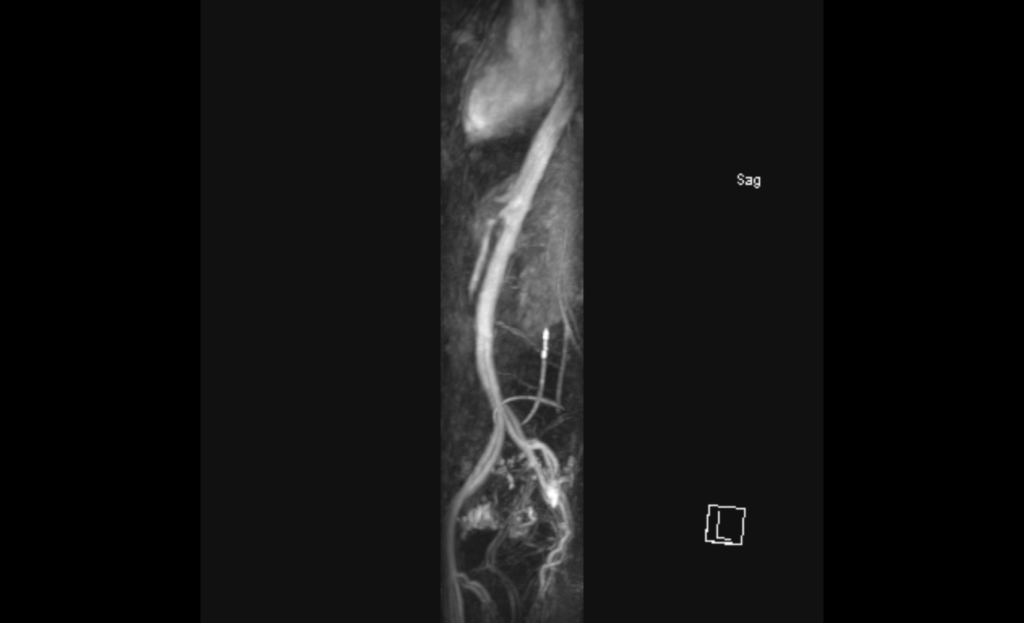

Update: Meine Aorta ist laut Facharzt wirklich dufte. Aber mein Gedärm wird nur halbherzig versorgt, da ich eine Stenose in der Arteria mesenterica habe (das unterbrochene Zipfelchen, das bauchwärts aus meiner Aorta rauskommt, zu sehen in der Sagittalebene). Eventuell durch Verklebungen im Bauch durch die vielen Kaiserschnitte? Verrückt, denn genau deshalb hab ich mir vor einer Weile eine Überweisung für eine Darmdurchleuchtung geholt – um schauen zu lassen, WO es klebt. Ich merke ja, DASS was klebt. Trotzdem gut und richtig, dass ich Kaffeesatzlesen nur bei mir selbst betreibe. Ein bisschen wie der Versuch, Landkarten zu verstehen, um am Ende im Graben zu landen und über sich selbst zu schmunzeln. ☺️